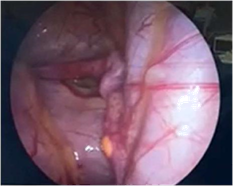

In our patient, exploratory laparoscopy was performed, which confirmed the presence of dysgenetic gonads. It was removed and histologically studied, which reported the presence of uterine tubes with fimbriae, without significant histological alterations. In both gonads, no tissue macroscopically compatible with the ovary was observed; microscopically, remains of ovarian parenchyma were observed, composed only of stroma and rete ovarii, without follicular structures or findings of malignancy (Figures 13).1–4

Figure 3 Uterus.